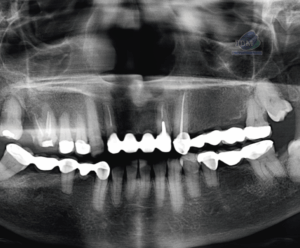

A la evaluación de la tomografía cone beam de campo mediano se puede observar que dicha pieza se encuentra caudal al ápice de las piezas 32, 31, 41, 42 y 43 con la porción coronaria en contacto y adelgazando la tabla ósea vestibular y la porción radicular se encuentra equidistante a ambas tablas óseas y la presencia de un foramen lingual. Se descartar cualquier relación con piezas dentarias vecinas